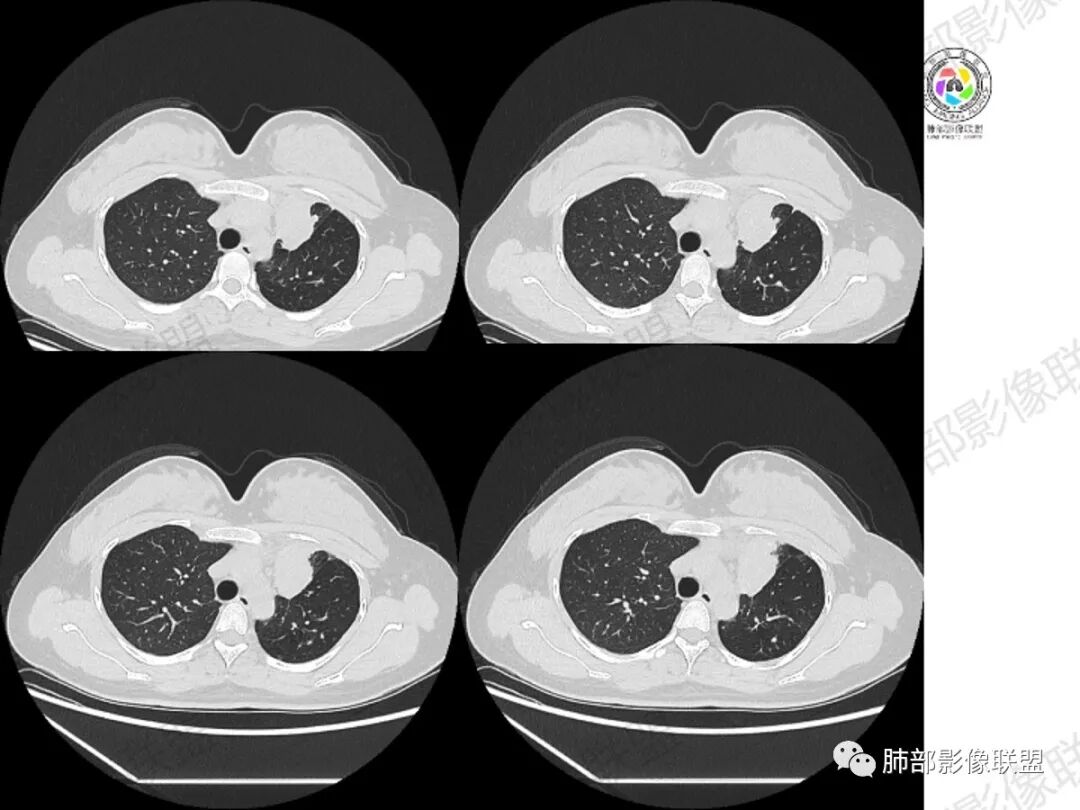

年轻女性,咳嗽咳痰一个月,左肺体积缩小,左肺尖部胸膜下实变影,宽基底与胸膜相贴,病灶边缘平直收缩,部分略膨隆,病灶下方可见支气管挤压,肺窗所示:周围伴有多发结节部分可见树丫征,纵隔窗可见病灶与纵隔胸膜黏连,部分与左肺动脉分界欠清,平扫密度尚均匀,增强扫描不均匀强化,内部可见多个低密度坏死,伴有条状血管影,纵隔淋巴结略有肿大。

胸部CT:左肺体积缩小,左肺上叶前段纵隔旁胸膜下大片实变影,边缘清楚、匀齐、平直收缩,部分略膨隆,周围多发结节、树芽卫星灶,纵隔窗病灶与纵隔胸膜黏连,实变内多发点状钙化。平扫密度尚均匀,增强扫描不均匀明显强化,多个低密度区,呈仙人掌样,伴有条状血管影,考虑慢性炎症伴左上叶前段支气管闭塞,TB?鉴别黏表、腺癌等。

周围多发小斑片,病灶内可见点状钙化,29岁女性,警惕结核;

5.块影周围“卫星灶”,密度及分布特点,更多见于结核,而非转移。